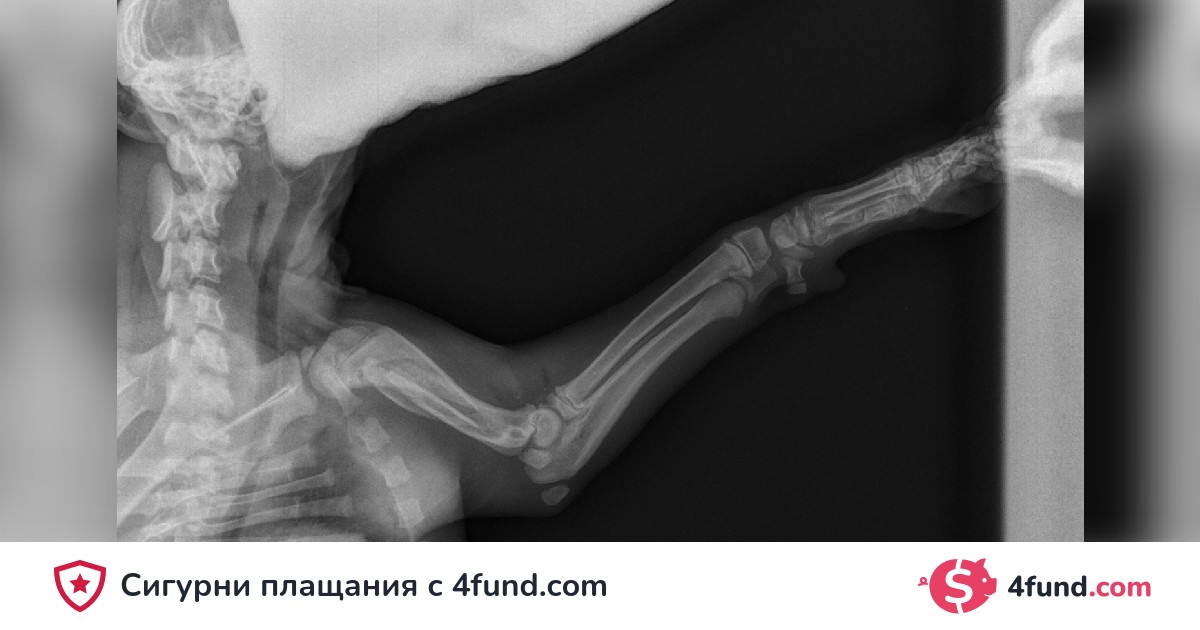

Операция Broken Homer

Добра сутрин малко кученце беше нападнато, за да я оперират, те ме помолиха 1400 плюс ДДС, знам как трябва да го направя, рискува ампутация...